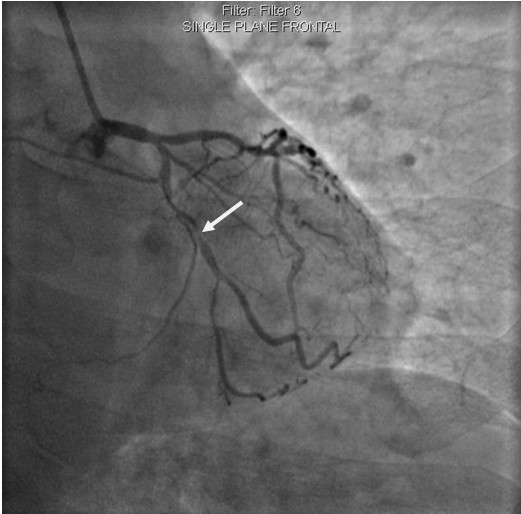

李先生蜘蛛位術前影像

李先生蜘蛛位術后影像

術前,翟光耀主任還親自為李先生復查冠狀動脈造影,造影結果顯示:患者的前降支、回旋支、右冠等冠脈三支嚴重病變、嚴重鈣化,且均為彌漫性長病變,最重處99%以上管腔極嚴重狹窄。翟主任仔細閱讀造影結果后指出:結合李先生的實際情況,雖然微創介入手術難度比較大,但仍可行;李先生心臟三支主干動脈均存在極其嚴重的狹窄,每一支動脈均至少植入2-3枚支架,根據患者的耐受情況,李先生可能需要分3次分別對三支動脈進行介入手術;考慮到李先生路途遙遠,病情嚴重,不宜反復奔波,并且患者迫切要求能夠徹 底解決病痛,在病情允許的情況下,如果手術順利,爭取為患者進行“一站式”手術,一 次 性解決全部三支動脈病變!

手術方案確定之后,在心血管內三科趙景新主任、介入醫學科富孝晨主任的配合下,翟光耀主任親自擔任主刀,分別依次對李先生的三支動脈進行了完全血運重建。由于手術進展順利,李先生術中沒有任何癥狀,耐受良好,于是成功的將三支動脈“一站式”治療!術中,由于李先生左主干遠端分叉處存在嚴重病變,翟光耀主任選擇國際指南推薦的DK-mini-Crush技術,確保了分叉處兩支主干開口均萬無一失。據悉,DK-mini-Crush技術是目前冠脈分叉病變領域最為復雜及難以掌握的介入技術之一,對手術醫生經驗、體力均提出了極大的挑戰。極為擅長復雜介入技術的翟光耀主任卻用嫻熟的技術確保了李先生手術的成功。

冠狀動脈嚴重鈣化合并狹窄病變是冠脈介入的一大難題,血運重建難度大,成功率低,并發癥發生率高,該例患者的成功救治標志著我院冠脈介入水平又躍上了一個新的臺階。